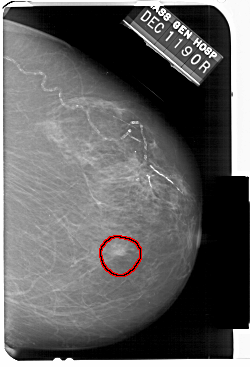

A_1511_1.RIGHT_MLO

RIGHT_MLO LINES 5146 PIXELS_PER_LINE 3541 BITS_PER_PIXEL 12 RESOLUTION 43.5 OVERLAY

FILE: A_1511_1.RIGHT_MLO.OVERLAY

TOTAL_ABNORMALITIES 1

ABNORMALITY 1

LESION_TYPE MASS SHAPE IRREGULAR MARGINS ILL_DEFINED

ASSESSMENT 4

SUBTLETY 4

PATHOLOGY MALIGNANT

TOTAL_OUTLINES 1

BOUNDARY